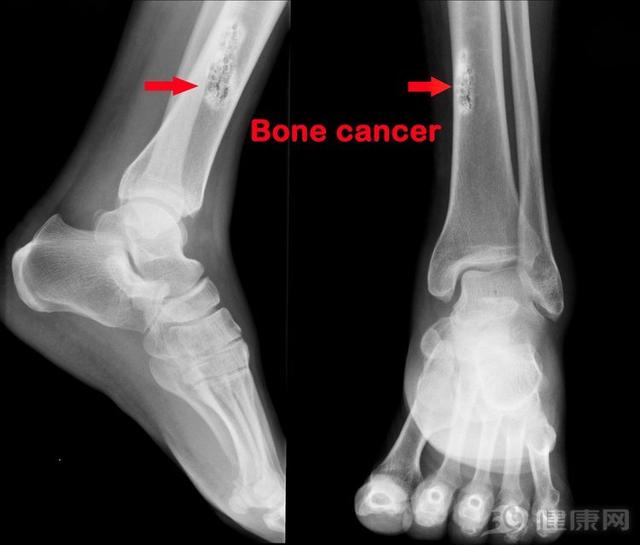

骨癌早期有哪些症状表现(腿痛得整夜睡不着)

2019年,医疗纪录片《人间世》第二季上线,第一集《烟花》,将镜头聚焦在上海市第一人民医院骨科骨肉瘤病房的患儿和他们的父母身上。这个病房里的患者都是孩子,最大十几岁,最小7岁,他们都身患一种叫做“骨肉瘤”的疾病。14...